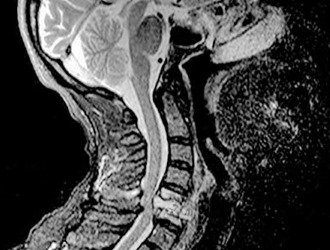

- Рентгенографию, которая позволяет обнаружить остеохондроз и деформации в позвоночнике;

- Томографию, помогающую определить наличие грыжи и степень патологии;